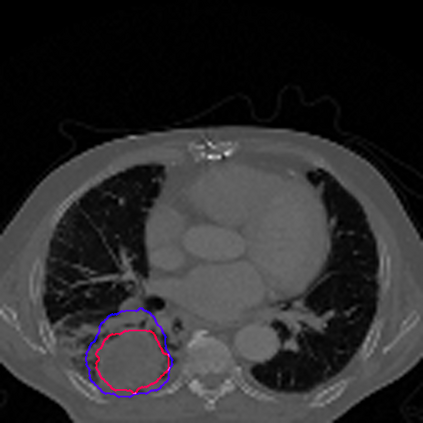

Lung cancer is a leading cause of death in most countries of the world. Since prompt diagnosis of tumors can allow oncologists to discern their nature, type and the mode of treatment, tumor detection and segmentation from CT Scan images is a crucial field of study worldwide. This paper approaches lung tumor segmentation by applying two-dimensional discrete wavelet transform (DWT) on the LOTUS dataset for more meticulous texture analysis whilst integrating information from neighboring CT slices before feeding them to a Deeply Supervised MultiResUNet model. Variations in learning rates, decay and optimization algorithms while training the network have led to different dice co-efficients, the detailed statistics of which have been included in this paper. We also discuss the challenges in this dataset and how we opted to overcome them. In essence, this study aims to maximize the success rate of predicting tumor regions from two dimensional CT Scan slices by experimenting with a number of adequate networks, resulting in a dice co-efficient of 0.8472.